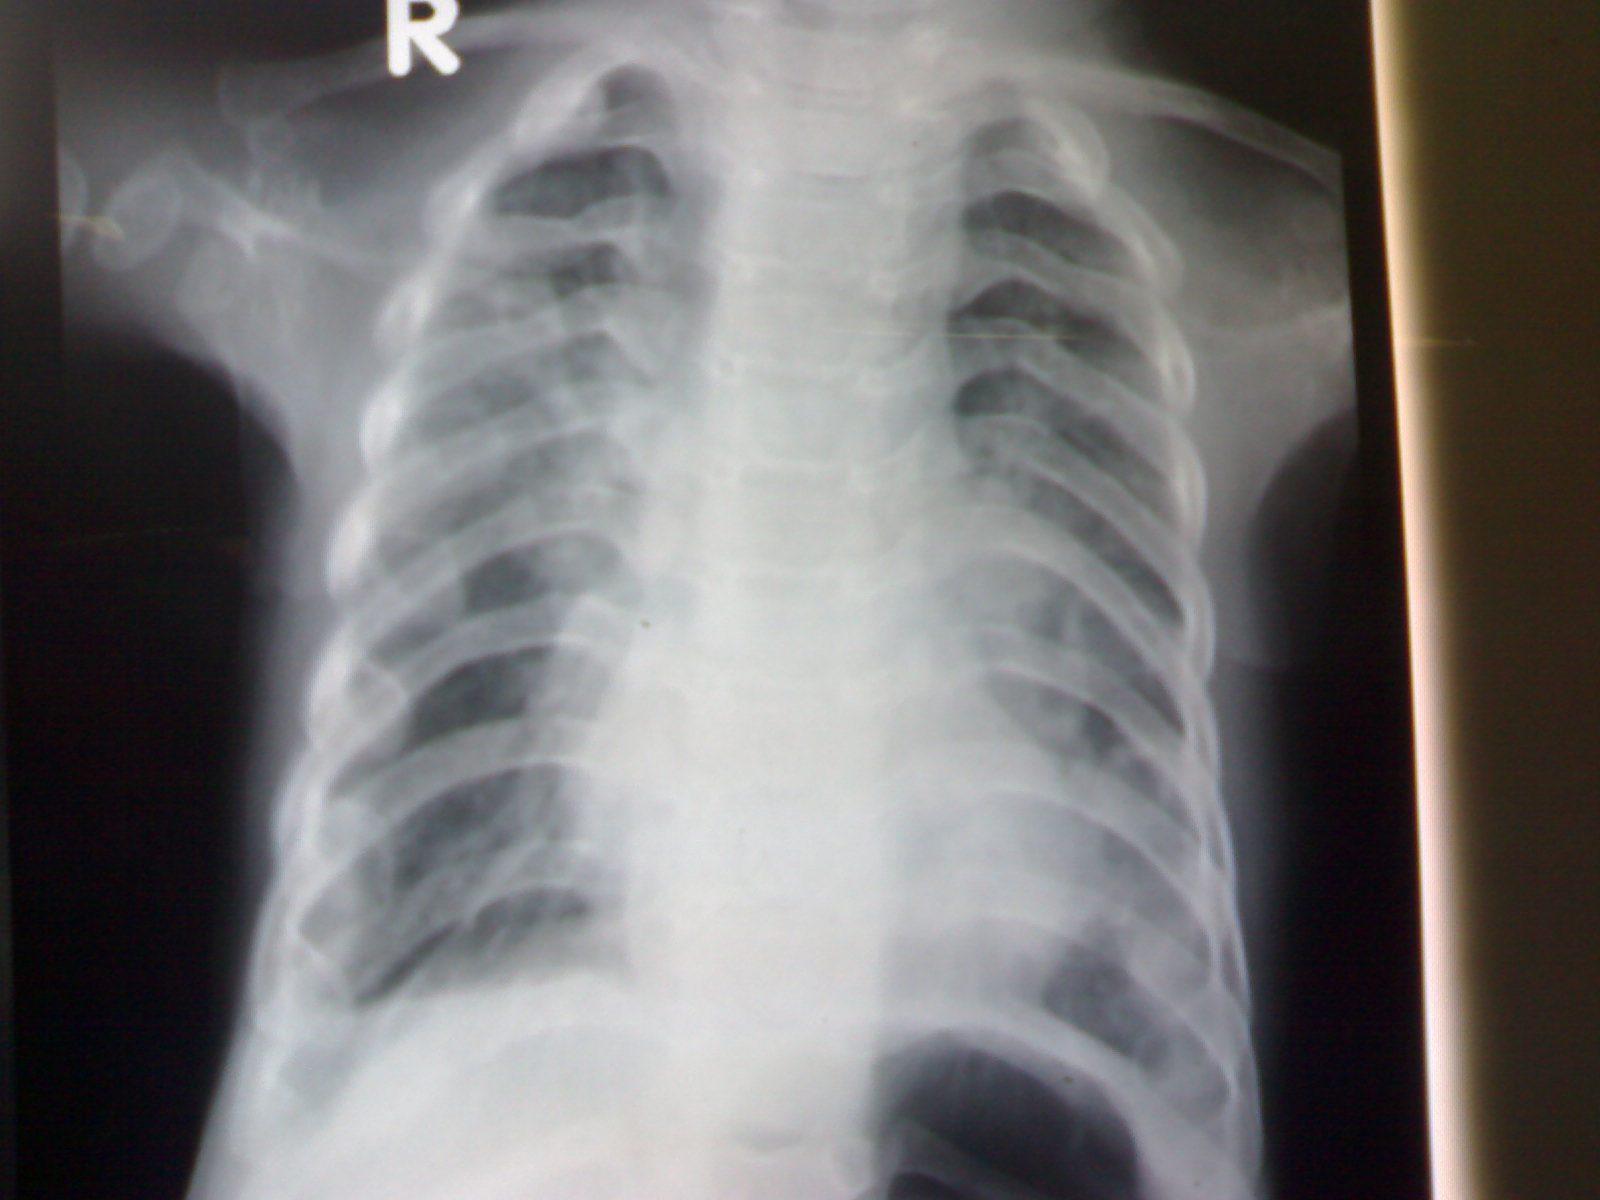

The chest roentgenogram reveals narrow thorax, broad, short and horizontal ribs and highly placed clavicle. The distal ends of ribs were widened and club-shaped and do not extend beyond the anterior axillary line. Diagnosis is Jeune syndrome or asphyxiating thoracic dystrophy. It is a rare autosomal recessive skeletal disorder characterized by a small thorax, short limbs, pelvic abnormalities {hypoplastic iliac wing}, and renal anomalies {1}. It has a varied clinical spectrum of manifestations. The disease is fatal to affected infants in early childhood in 70 percent of cases, mostly due to asphyxia secondary to a small thoracic cage. All have small chests clinically, but the degree of respiratory distress varies from negligible to rapidly lethal {2,3}. Occasional abnormalities include polydactyly, pancreatic fibrosis, situs inversus and deformed teeth {1}. Treatment is mainly supportive although authors have reported utility of lateral thoracic expansion {4}. Because the disease is inherited with an autosomal recessive pattern, there is 25 percent chance of recurrence in the subsequent pregnancy {1}. Genetic counseling and prenatal diagnosis may be offered in selected cases.